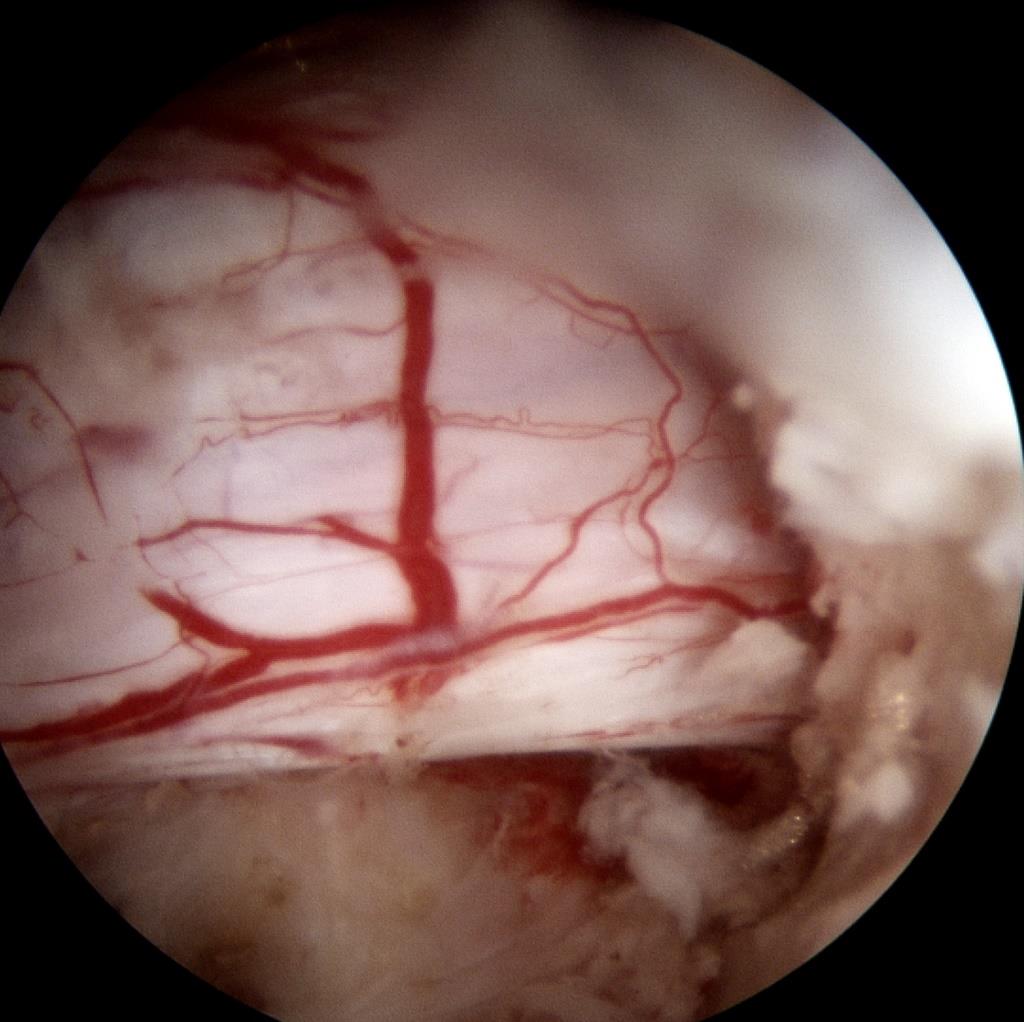

• 脊柱内镜侧后路联合减压术治疗腰神经根双卡综合征的临床疗效观察

2025, 31(12):25-32. DOI: 10.12235/E20250012

摘要 (122) HTML (46) PDF 10.14 M (90) 评论 (0) 收藏

摘要:目的 观察脊柱内镜侧后路联合减压术治疗腰神经根双卡综合征(DCS)的临床疗效、可行性、安全性和有效性。方法 回顾性分析2018年9月-2023年9月于该院就诊的50例腰椎退行性病变致腰神经根DCS患者的临床资料,根据手术方法不同,将患者分为观察组(37例)和对照组(13例)。观察组行脊柱内镜侧后路联合减压术治疗,对照组行非手术治疗。比较两组患者治疗前、治疗后1周、治疗后3个月、治疗后6个月和治疗后12个月的疼痛视觉模拟评分法(VAS)评分、Oswestry功能障碍指数(ODI)和日本骨科协会(JOA)评分。末次随访时,采用改良Macnab标准,评估临床疗效;采用腰椎MRI检查,评估椎间隙高度和椎间盘退变改良Pfirrmann分级。比较两组患者治疗的安全性(包括:并发症发生情况、复发情况和转手术治疗情况)。结果 50例患者均顺利完成治疗。两组患者术后VAS评分和ODI呈下降趋势,JOA评分呈升高趋势,观察组术后各时点VAS评分和ODI明显低于术前,且明显低于对照组,术后各时点JOA评分明显高于术前,且明显高于对照组,差异均有统计学意义(P < 0.05);观察组优良率为86.49%,明显高于对照组的76.92%,差异有统计学意义(P < 0.05);两组患者末次随访时,椎间隙高度和椎间盘退变Pfirrmann分级比较,差异均无统计学意义(P > 0.05)。两组患者围手术期均未出现神经损伤和脑脊液漏等严重并发症,观察组术后1例出现下肢放射性疼痛;观察组1例术后3个月出现腰椎间盘再突出;对照组有3例转手术治疗。结论 与非手术治疗相比,脊柱内镜侧后路联合减压术可更为安全、有效地缓解腰神经根DCS患者的疼痛,改善下肢功能,且早、中期临床疗效好。值得临床推广应用。